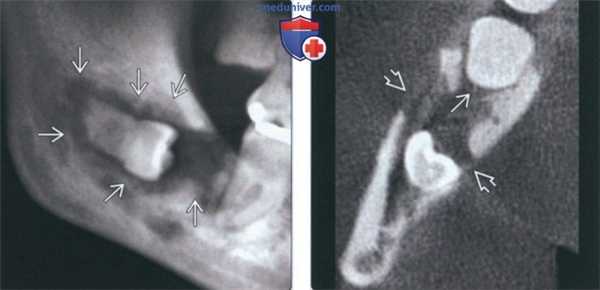

(Слева) На панорамной рентгенограмме определяется ЦМР, связанный с импактным 3-м моляром нижней челюсти справа. Опухоль выглядит как хорошо отграниченное просветление не правильной формы, связанное с коронкой и продолжающееся к корню. Эту опухоль, возникшую, вероятно, в зубной кисте или ке-ратокисте, можно спутать с остеомиелитом.

(Справа) На аксиальной КЛКТ у этого же пациента определяется распространение опухоли к пространству периодонтальной связки второго моляра. Обратите внимание на деструкцию кортикальной пластинки.3. КТ при центральном мукоэпидермоидном раке челюсти:

(Слева) На КЛКТ (профильный срез) у этот же пациента определяется хорошо отграниченное поражение в области коронки зуба. Нижний и язычный край имеют инфильтративный характер, щечная кортикальная пла стинка разрушена. Обратите внимание на интактный нижнече люстной канал внизу.

(Справа) На трехмерной реконструкции (КЛКТ, вид под углом) у этот же пациента визуализируется четкий мезиальный край кистозного образования, распространяющется в позадимолярную область.1. Общая характеристика: